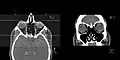

CT scan of the paranasal sinuses with coronal reconstruction (right) and axial planning data (left).

CT scan of the paranasal sinuses with coronal reconstruction (right) and axial planning data (left). Sectional Planes of the Brain